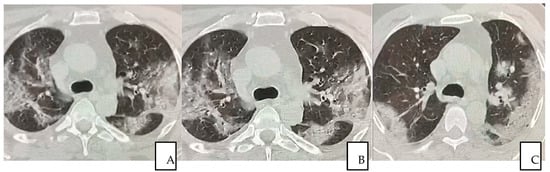

Serial chest CT scan during recovery from COVID-19 were performed to evaluate lung abnormalities displayed as ground-glass opacity with the development of white net pattern and increased consolidation (i.e., more extensive lung involvement), and following resolution. The severity of lung damage and the differences between patients who recovered with conventional treatment and the patient received additional autologous plasma and stem cells treatment were assessed and described by comparing CT scan images. It is worth emphasizing that patients showed interstitial lung damages even long after COVID-19 resolved (12 months), as reported in this study (Figure 4A–C).

Figure 4.

(A–C) A 56-year-old man from “SG Moscati Hospital”, Taranto, presented with fever, cough, and chest pain. Pulmonary HRCT at presentation on 3 March 2020 showed extensive peripheral predominant ground-glass opacities in both upper lobes (A); On 26 March 2020, a follow-up HRCT showed similar anomalous ground glass opacities (B) HRCT obtained on 14 May 2020 showed organizing changes with decrease in extent of the ground-glass opacities and increasing parenchymal consolidations (C).